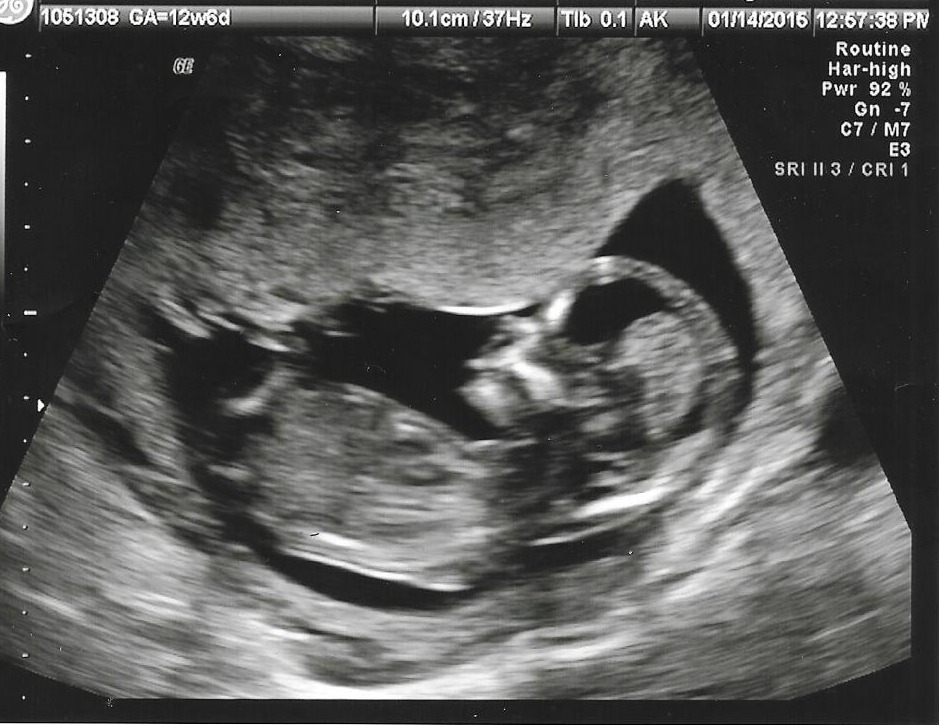

Attachment 23158

Leaning girl

I see a boy :)

Yeah the white line you are talking about is just noise from movement. Wish it was the nub so we could give you a better guess. Im looking at your cropped in picture and I would lean boy.

:D What makes you lean pink?